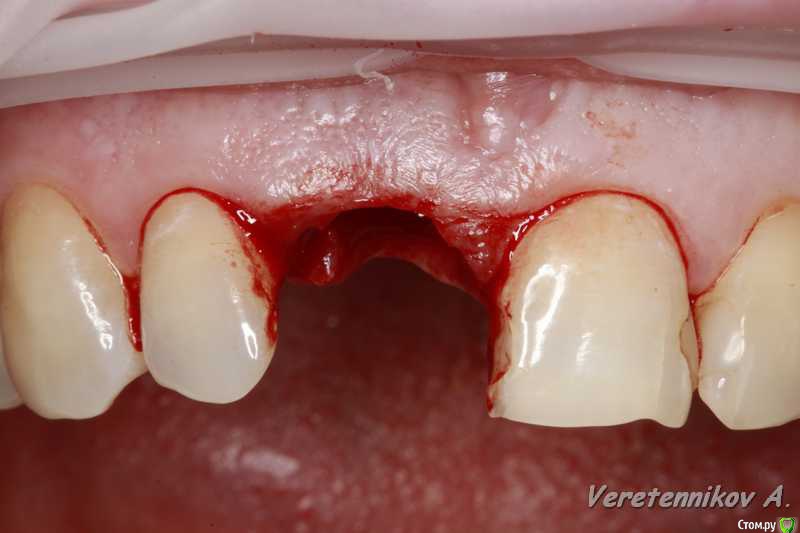

Популярный пост an_ver Опубликовано 15 января, 2016 Популярный пост Поделиться Опубликовано 15 января, 2016 11,жил долго и счастливо..но тут Новый год(((, скол ниже уровня ЦЭС на 3 мм...от экструзии отказалась.Из своего зуба сколхозил шаблон,чтоб наверняка. Удалил,кюретаж,вестибулярка целая, SPI 4.2*13 мм,с бугра ССТ,на всякий)),в щели Апатос,врем.абатмент,врем.коронка из своего зуба. 1ч.20мин.)) 27 Ссылка на комментарий

k.t.m. Опубликовано 15 января, 2016 Поделиться Опубликовано 15 января, 2016 в щели апатос,сст в сформированный карман! Андрей красиво и все по пунктам,как так вышло что сосочек порвался?может не стоило так глубоко сст заводить? 1 Ссылка на комментарий

an_ver Опубликовано 16 января, 2016 Автор Поделиться Опубликовано 16 января, 2016 (изменено) в щели апатос,сст в сформированный карман! Андрей красиво и все по пунктам,как так вышло что сосочек порвался?может не стоило так глубоко сст заводить?Чесно,фиг знает((( тока счас обратил внимание,наверно 15С орудовал глубоко (набор Деплер для туннеля в клаве был),((( немного лоскут перфорнул...если кто заметил,решил глубже завести ластик сст Изменено 16 января, 2016 пользователем an_ver Ссылка на комментарий

an_ver Опубликовано 16 января, 2016 Автор Поделиться Опубликовано 16 января, 2016 Клёво!!!Можно вопрос: как сст всовывали ?Просто опыта в этом аспекте очень мало и понятие "в щели" не совсем понятно.СпасибоВ щели: это свободные обьем лунки,после установки импланта,т.е. все пустоту забиваем графтом (Апатос). По ССТ: скальпель 15С, параллельно кости осторожно,маятниковыми движениями,до уровня прикрепления или глубже формируете карман,вкол с вестибулярки-выкол в лунке,вкол в сст,выкол там же,далее вкол внутри кармана и затягиваете сст...но проще посмотреть...сейчас А.Смолякова по рецессии выложила видео,принцип такой же 2 Ссылка на комментарий

an_ver Опубликовано 16 января, 2016 Автор Поделиться Опубликовано 16 января, 2016 перфо не заметил,но понял теперь почему так глубоко сст!ждем динамики!Перфо-второй шов,ниже Ссылка на комментарий